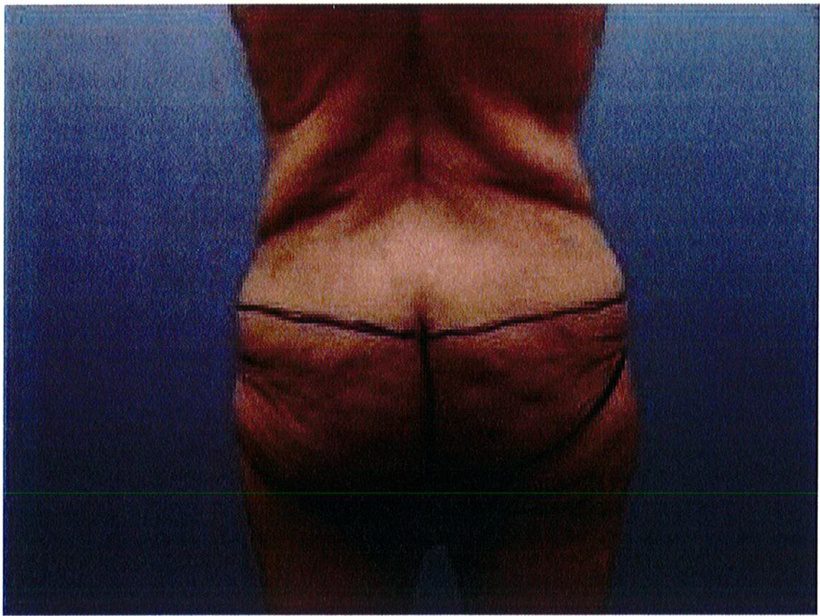

Đối tượng lý tưởng cho phẫu thuật này là bệnh nhân có vùng da và mô mềm vùng thắt lưng/mông dư thừa nhưng mông dẹt và gần như không có điểm hình chiếu. Tiêu chuẩn này có thể được xác định bằng cách dùng hai tay sờ và véo da đồng thời (Hình 2). Quy

Bệnh nhân được đánh dấu vùng phẫu thuật ở tư thế đứng. Điểm hình chiếu của mông được xác định, như cách mà tác giả Cen- teno và Mendieta đã mô tả, là điểm thuộc đường đi từ mấu chuyển tới xương cụt. Đường này xác định điểm hình chiếu của mông sau phẫu thuật.

Đế giải quyết vấn đề này, chúng tôi thường yêu cầu bệnh nhân hơi nghiêng người về phía đối diện khi chúng tôi thực hiện nghiệm pháp và đánh dấu ngay lúc đó, bên đối diện cũng được thực hiện tương tự. Tiếp tục đứng ở phía sau bệnh nhân và thực hiện nghiệm pháp tương tự để đánh dấu đường rạch da ở phía mông (Hình 3). Phần mô cạnh đường giữa thường dính chặt hơn với tổ chức phía dưới, nên sẽ lấy được ít tổ chức. Sau đó, cân chỉnh lại đường vẽ phía sau và hai bên để tạo thành một chuỗi đường liên tục. Phần được đánh dấu vừa rồi là phần sẽ rạch da và sau đó khâu nối bằng các mũi purse-string. Có thể dễ dàng thấy được khi nhìn từ phía sau thì phần tổ chức cần cắt bỏ sẽ có dạng cánh bướm, đóng vai trò như môt khu vực để neo giữ

Bằng cách sờ và véo da đồng thời bằng hai tay (hình 2) ở vị trí đường nách giữa, chúng ta đánh dấu phần da tiếp xúc với ngón trỏ và ngón cái, nối chúng với nhau tạo thành 2 đường. Hai đường này chính là hai đường mổ sau này. Tuy nhiên khi Bác sĩ thực hiện, bệnh nhân thường có xu hướng ‘hỗ trợ’ chúng ta, và vô tình nghiêng người về phía đó, khiến lượng mô chúng ta véo được nhiều hơn mức thực tế

Hình. 2. Nghiệm pháp véo da bằng hai tay được thực hiện ở đường nách trước. Để bệnh nhân nghiêng người sang bên đối diện để tránh cắt đi quá nhiều mô.

Hình. 3. Nghiệm pháp tiếp tục được thực hiện ở vùng mông để đánh dấu đường rạch da.

Hình. 4. Đánh dâu trước phâu thuật. Khu vực khoanh tròn màu tím chính là vùng được làm đầy bằng vật liệu tự thân bằng mô tự thân. Cần đánh dấu khi bệnh nhân đứng do da bệnh nhân rất chùng.